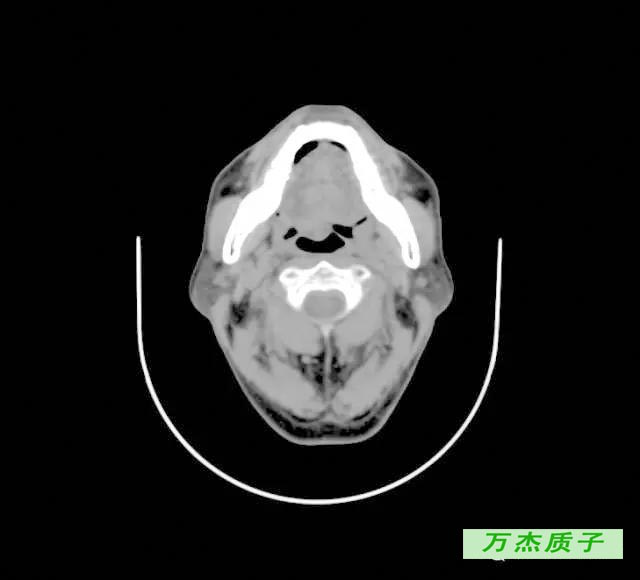

舌癌治愈率是多少 发布时间: 61次浏览 舌癌大家不会陌生,它是口腔颌面部常见的恶性肿瘤,发病率越来越高,严重的危害了我们的健康,有些舌癌患者会担心一个问题,舌癌的治愈率是多少,这关系到患者的人身安全。 舌癌的颈淋巴结转移率为29%~38%,与病程早晚期相关。治疗舌癌,先采用放射治疗而不应急于手术。直径在2厘米以下的治愈率,可高达%。 舌癌治疗 ( 一 ) 舌癌的一般疗法 (1) 舌癌患者因舌痛、舌肿大、溃烂、出血等影响进食 , 进食可以流质和半流质为主。

舌癌临床表现 编辑 播报 1肿瘤多发生于舌缘,其次为舌尖、舌背及舌腹等处,可有局部白斑病史或慢性刺激因素。 2常为溃疡型或浸润型,生长快,疼痛明显,浸润性强。 3可有舌运动受限、进食及 吞咽困难 。 4早期常发生颈淋巴结转移。舌癌诊疗知识 就诊科室: 肿瘤科 口腔科 治疗费用: 不同医院收费标准不一致,市三甲医院约( —— 元) 治愈率: 治疗周期: 治疗方法: 药物、手术治疗舌癌的治愈率有多大? 如果不能彻底治好,大约能活多久? _百度知道 舌癌的治愈率有多大? 如果不能彻底治好,大约能活多久? 首页 在问 全部问题 娱乐休闲